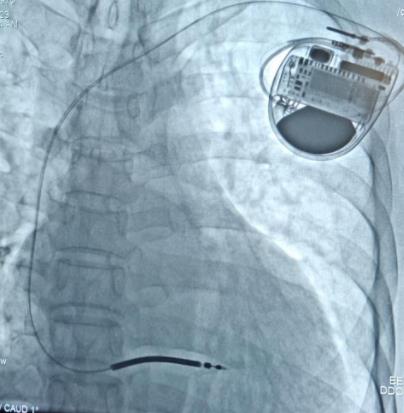

▲术后影像图

手术过程中,起搏电生理介入治疗团队依靠过硬的技术储备和丰富的操作经验,成功为刘先生进行植入型心律转复除颤器(ICD)手术,术中刘先生各项指标参数良好,血压、心率正常,手术历时1个小时,术后恢复良好,目前已办理出院。

甘剑挺介绍,80%以上的心源性猝死都是由于室速、室颤等恶性心律失常引起,对于易出现恶性室性心律失常的心脏病患者,不可能永远等待医生电除颤。因此,患者就需要一种可以随身携带的除颤器——植入式心律转复除颤器(ICD),这是心源性猝死高危患者的首选治疗方法。当发生恶性心律失常时无需医师在场,植入式心律转复除颤器(ICD)可及时自动为患者转复心律,通俗地说它就是装在人体体内的一个除颤仪,在心脏体内建立了一个“急救室”,被称为“心脏守护神”。